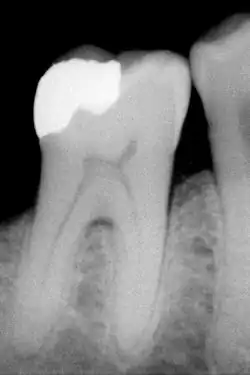

Radiographie d'une molaire obturée avec un amalgame.

C'est le matériau le plus ancien. Couramment appelé plombage, il ne contient pas de plomb. L'amalgame dentaire est constitué de mercure, d'argent, de cuivre, d'étain, de zinc… La proportion de ces métaux détermine le type d'amalgame. Les amalgames de dernière génération appelés « HCSC » (pour High copper single composition) sont à haute teneur en cuivre.